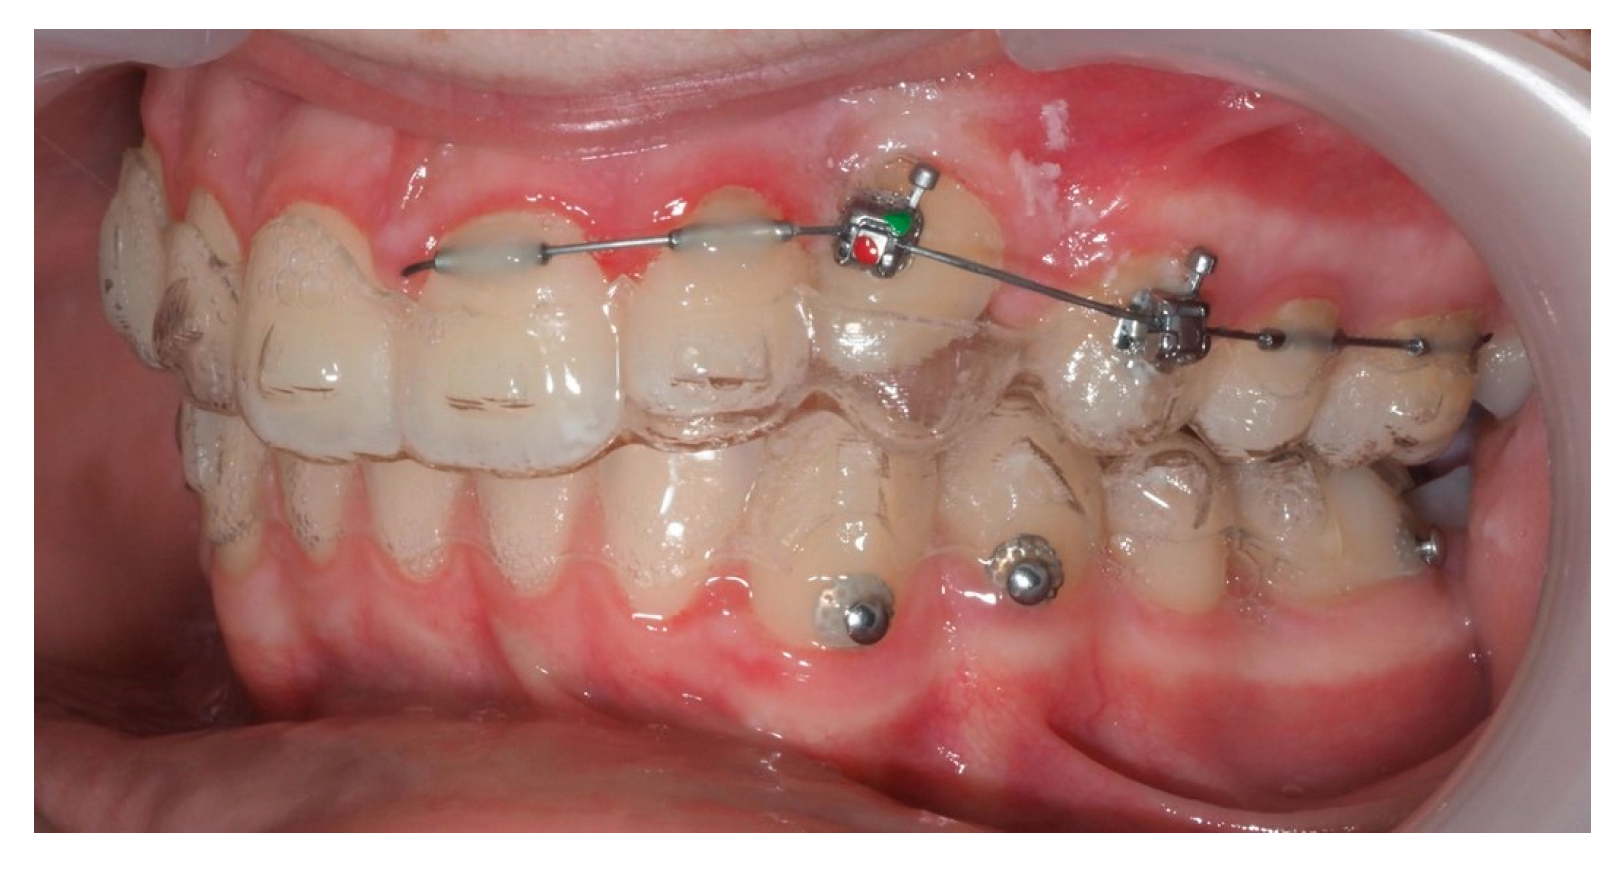

3.2. Representative Clinical Case

A 13-year-old male patient presented with Class II Division 2 malocclusion, a bilateral Class II sagittal relationship, and retroclined incisors. Cone-beam computed tomography revealed a palatally impacted maxillary left canine (tooth 23), with its cusp located palatally to the apical half of the left lateral incisor. The root exhibited significant apical curvature, extending toward the floor of the maxillary sinus (Figure 12 and Figure 13), making spontaneous eruption unlikely.

Figure 12.

Initial intraoral lateral photo.

Approximately 7 months later, a palatal mini-implant was placed between teeth 24 and 25, serving as stable anchorage for distal traction using an elastic chain, which was replaced monthly (Figure 15). This movement positioned the canine away from the lateral incisor root. Aligners were customized and adjusted throughout treatment.

Figure 15.

Adjusted aligners, palatal mini-implant, and elastic chain used for distalizing the canine; 7 months after the surgery.

Following initial distalization, a sectional fixed appliance was bonded from tooth 11 to 26. On tooth 24, a bracket with a metallic ligature was used to support Class II elastics. Mini-tubes were bonded on teeth 22, 25, and 26, and the aligners were trimmed accordingly (Figure 16). A ligature wire connected the palatal button on the canine to a 0.014” nitinol archwire (Figure 17).

Figure 16.

Sectional fixed appliance from teeth 11 to 26, with support for Class II elastics to improve sagittal relationship; 14 months after the surgery.